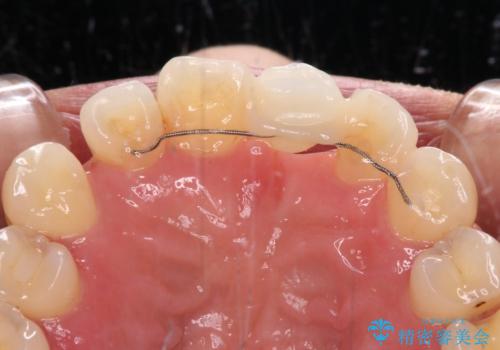

矯正治療により前歯横幅のバランスを整えた後に、上顎前歯をオールセラミックブリッジにて補綴治療を行うこととしました。

舌突出癖により、上下前歯が突出して離開してしまったため、舌のトレーニングを徹底的に行いました。